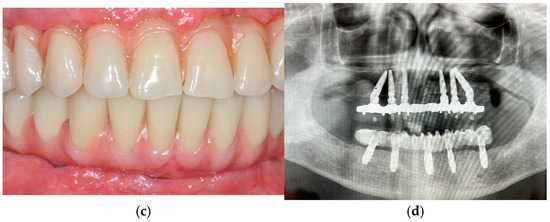

The Effectiveness and Predictability of BioHPP (Biocompatible High-Performance Polymer) Superstructures in Toronto-Branemark Implant-Prosthetic Rehabilitations: A Case Report

3. Case Presentation